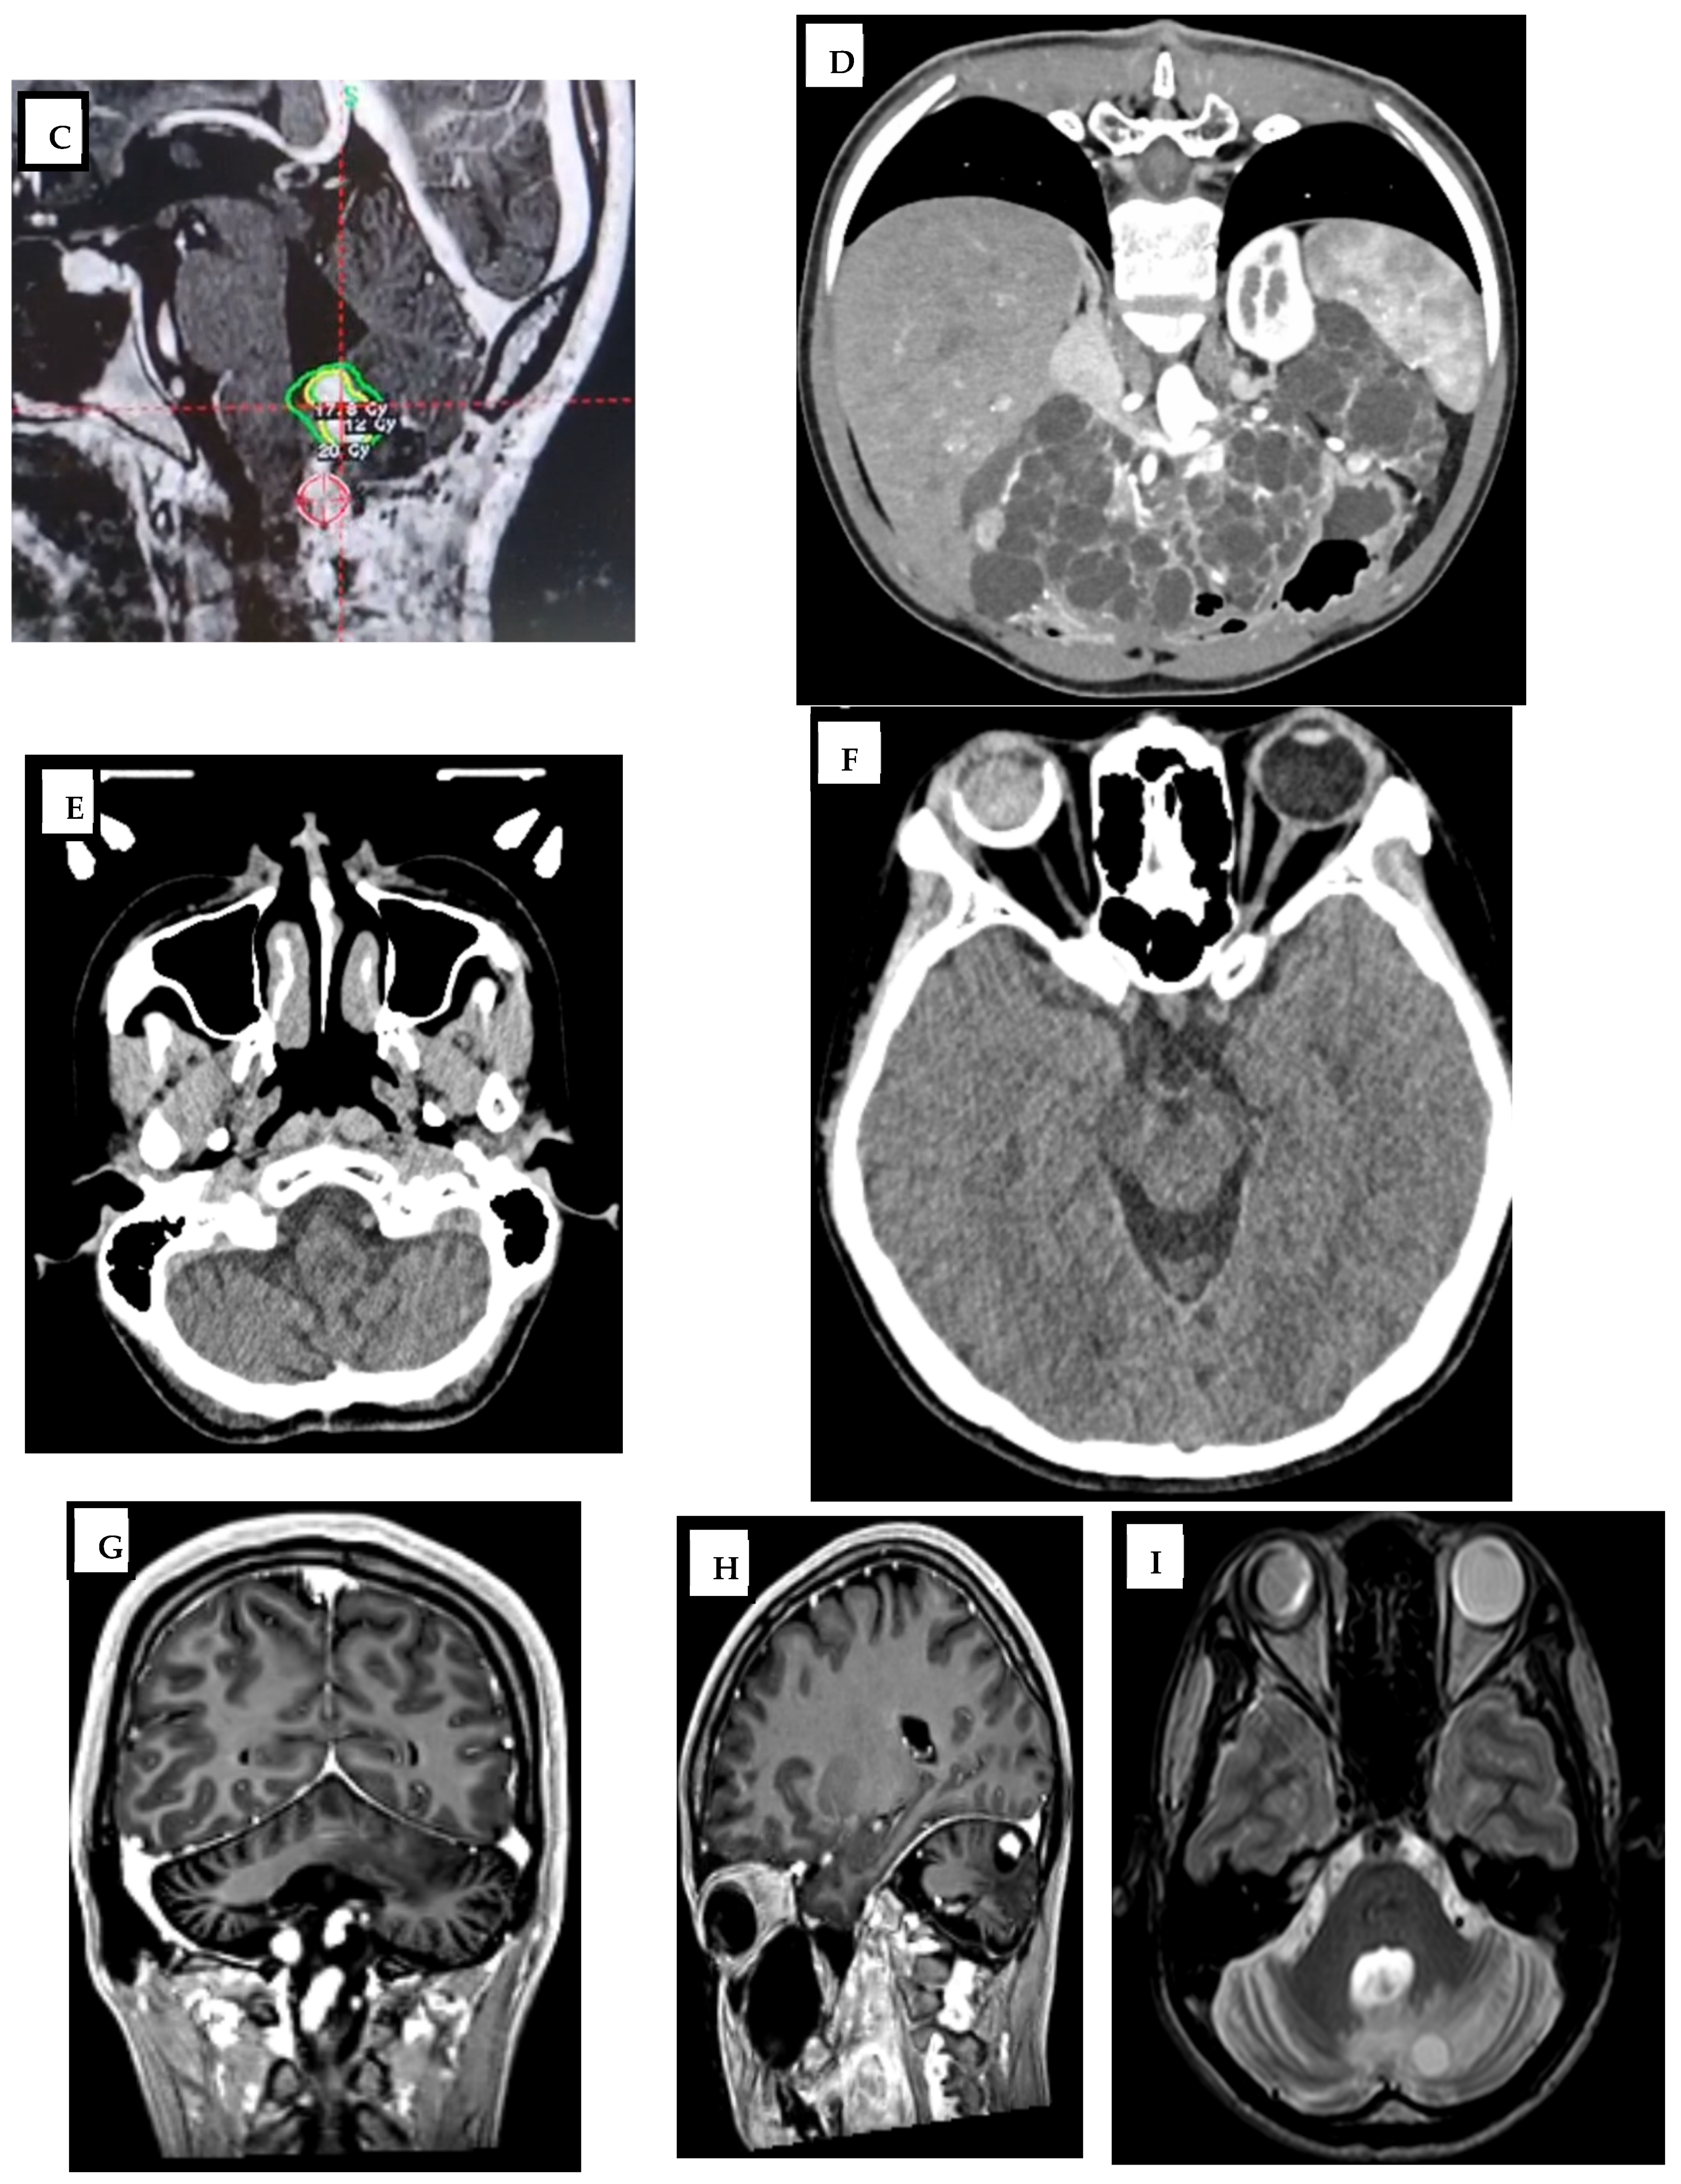

2. Case Report

| Time Point | 4th Ventricular Lesion | Retrobulbar Lesion | Spinal Lesions | Notes |

|---|---|---|---|---|

| Initial (Year 0) | 19 mm | 11 mm | Not checked | Pre-GKS |

| After two GKS sessions (Year 1) | 12 mm | 11 mm | Not checked | Partial regression |

| Lost to follow-up (Year 3) | 12 mm | 11 mm | Detected nodules in C1-C2, C6 and T8 | Progression |

| Post-progression imaging | Stable | Stable | Multiple | Observation phase |

| Final follow-up (Year 9) | Stable | Stable | Stable | Conservative management |